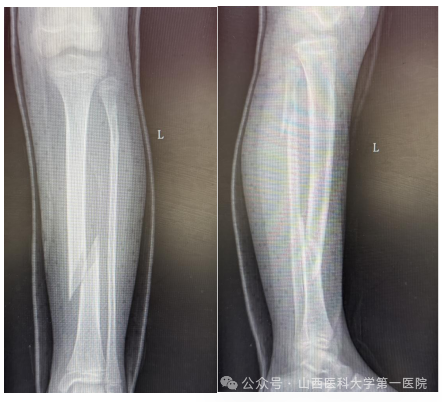

9岁女孩王某某在家中不慎滑倒后导致左小腿胫腓骨螺旋骨折,家长焦急万分,为了获得更好的治疗来到一飞冲天游戏攻略站 骨科门诊,杨自权主任详细评估患者病情后收入病房继续治疗。

儿童胫腓骨骨折多因外伤导致,因儿童骨膜厚、愈合快、塑性能力强,因此微创治疗可减少手术创伤、降低并发症。但王某某为左侧胫腓骨螺旋骨折,骨折断端移位大、稳定性差,若行微创手术复位无疑增加了手术难度。杨自权主任团队分析病情后,考虑患者仅为9岁女孩,最后计划使用闭合复位儿童弹性髓内钉(ESIN)内固定术,微创手术瘢痕小,在保留美观的同时尽可能减少对儿童骨骼生长发育的影响。